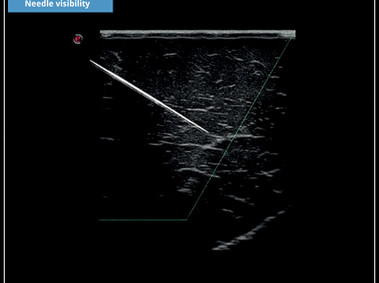

Needle Visibility – A clear and enhanced image of the target area during intervention procedures regional anaesthesia.